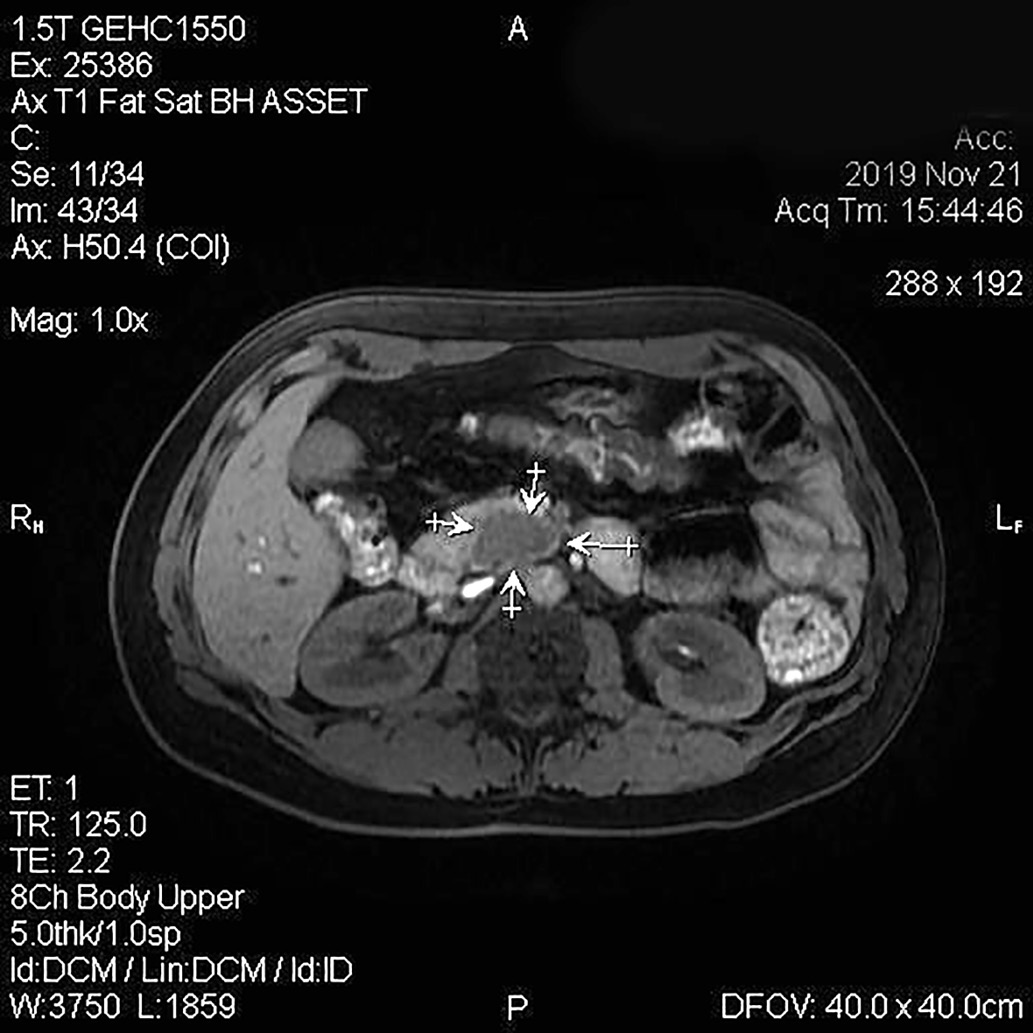

2. Рисунок 2. Магнитно-резонансная томография органов брюшной полости с контрастным усилением. Стрелками показано образование в поджелудочной железе. | |